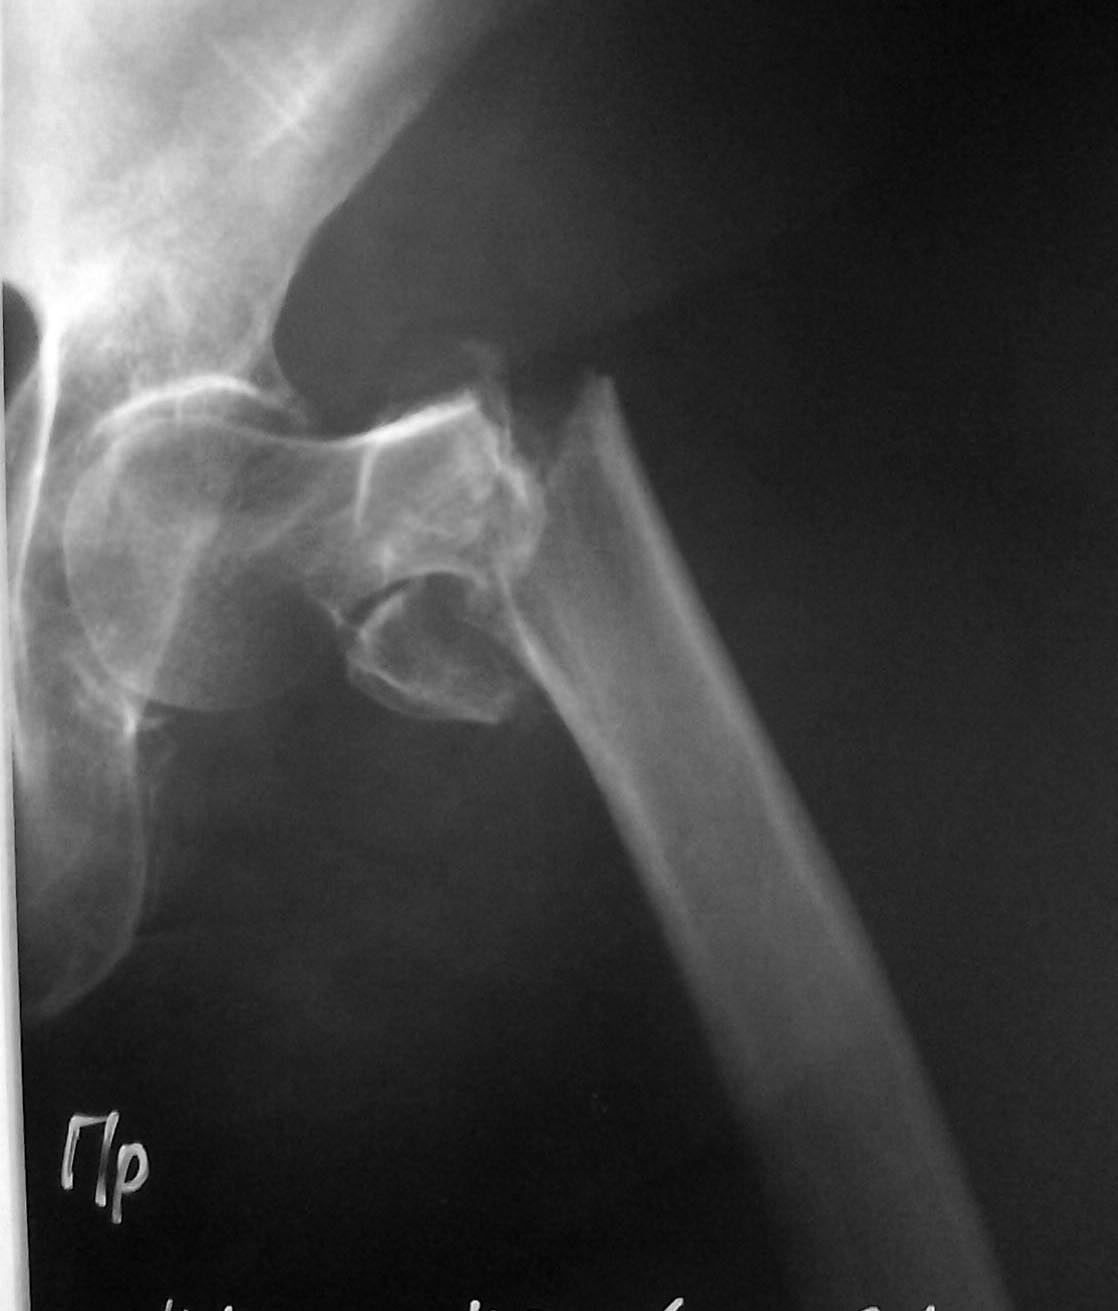

Чрезвертельный перелом

Больная 77 лет чрезаертельный перелом, коллегам просьба помочь в выборе метода лечения

Что доступно на месте, чем обычно фиксируете вертельные переломы? И чем обусловлен вопрос - этот перелом выглядит каким-то необычным?

Так, абстрактно - какой-нибудь PFN, если есть такая возможность. Или DHS.